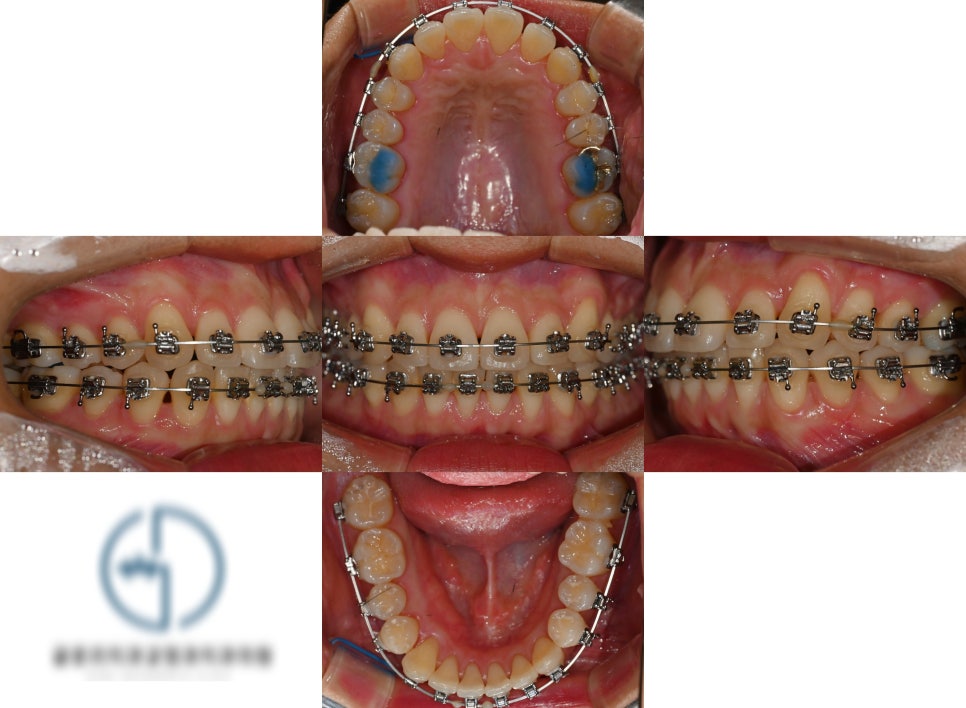

2. 장치 부착

전체적인 치열의 이동이 개선이

되어야 된다는 진단 결과에 따라

전체 치열에 장치를 붙여줍니다.

브라켓을 치면에 붙여 놓고

어금니 쪽에 파란색 레진을 올려

위턱과 아래턱 사이의 교합을 수정해 나갑니다.

이러한 과정들을 통해 빽빽한 곳과

어긋난 이 사이들을 가지런하게

배열할 수 있는 공간을 만드는 역할을 하며

필요에 따라 중간에 제거하기도 합니다.

진료 중간 중간 촬영한 f.u 사진들 입니다.

진단 결과에 따라서 조금씩

치열이 개선 되는 것을

확인 할 수 있습니다.

이렇게 재교정의 경우에는 큰 단위보단,

작은 단위에서 조금 더 세심한 조정이

필연적 입니다.

치료가 종료되면서 말끔히 해결된

모습을 볼 수 있습니다.

글 초반부에 보여드렸던 사진에서

볼 수 있었던 특정 부위에서

교합이 닿지 않는 곳 또한

정상 교합으로 바뀌었습니다.

동시에, 치열이 흐트러지는 것을

최소화 할 수 있는 유지장치까지

같이 제작하여 붙여줍니다.